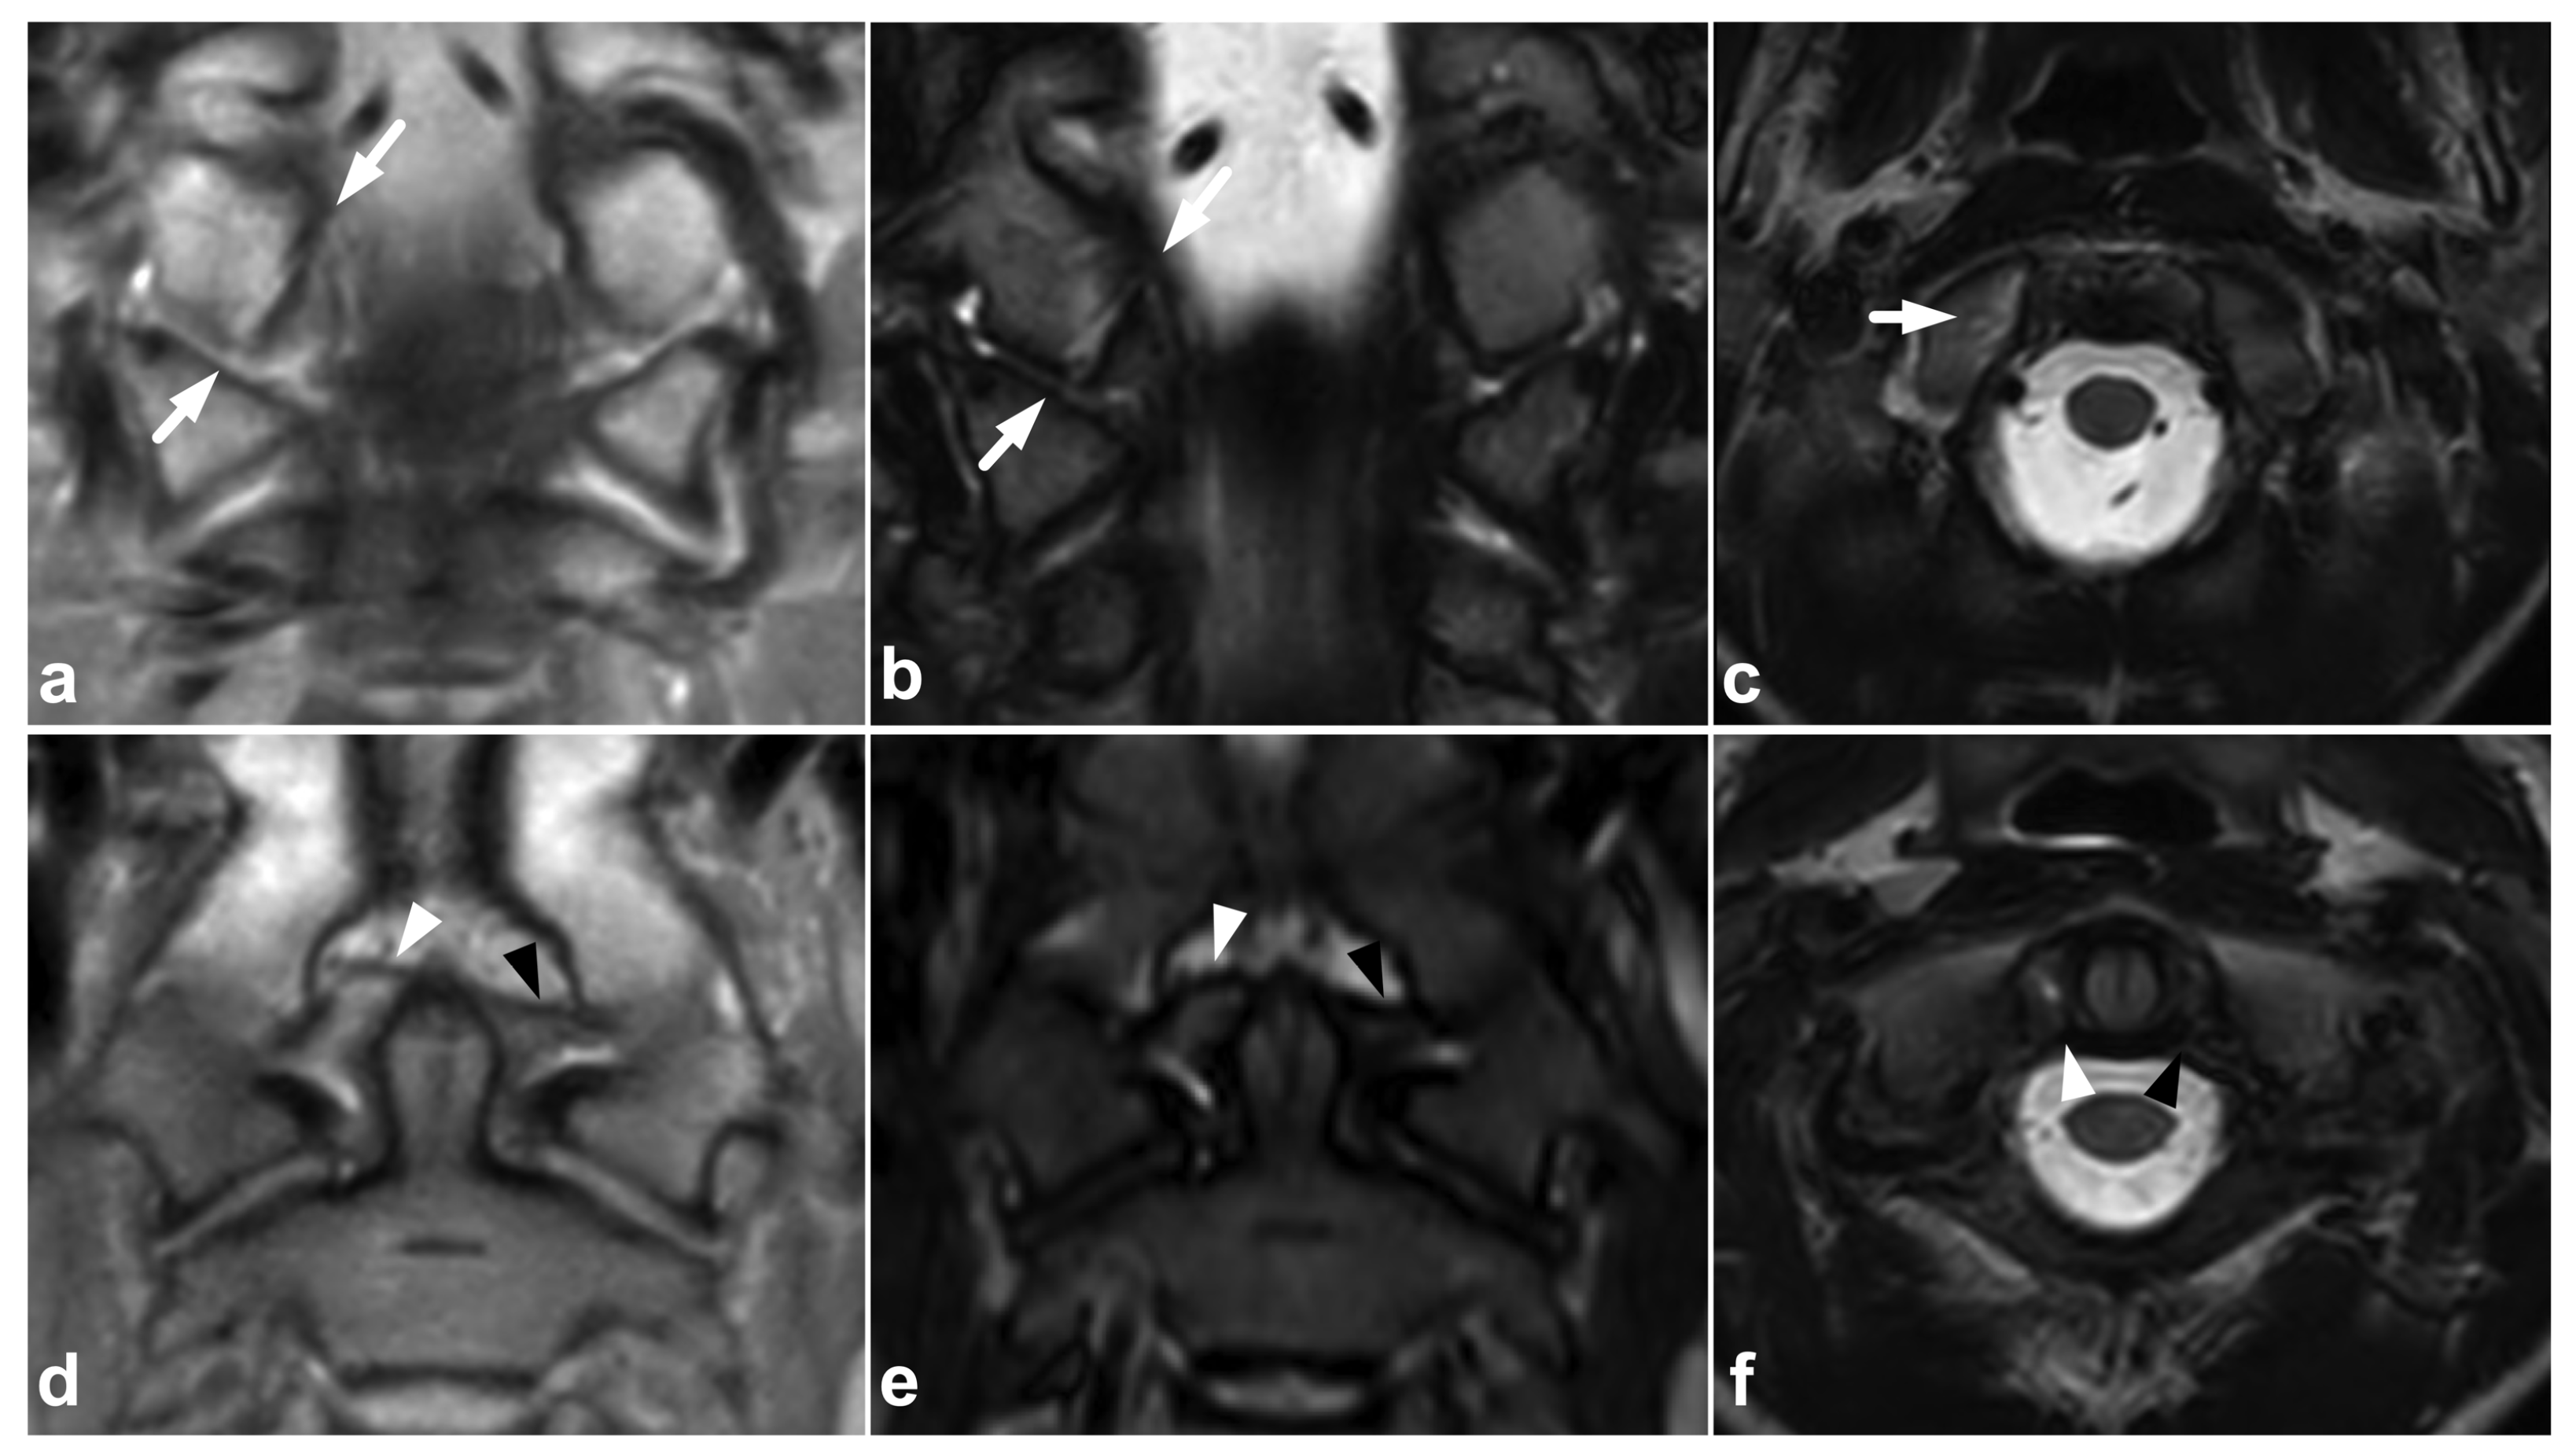

Figure 4.

(a) Coronal PD-weighted. (b) Coronal T2-weighted. (c) Axial T2-weighted. (d) Coronal PD-weighted. (e) Coronal STIR. (f) Axial T2-weighted. A 13-year-old male, motor vehicle accident. Avulsion fracture (arrows) of the right alar ligament origo in the occipital condyle, minor dislocation. The right alar ligament (white arrowheads) is swollen and loose but not completely torn. An intact left alar ligament is marked with black arrowheads.